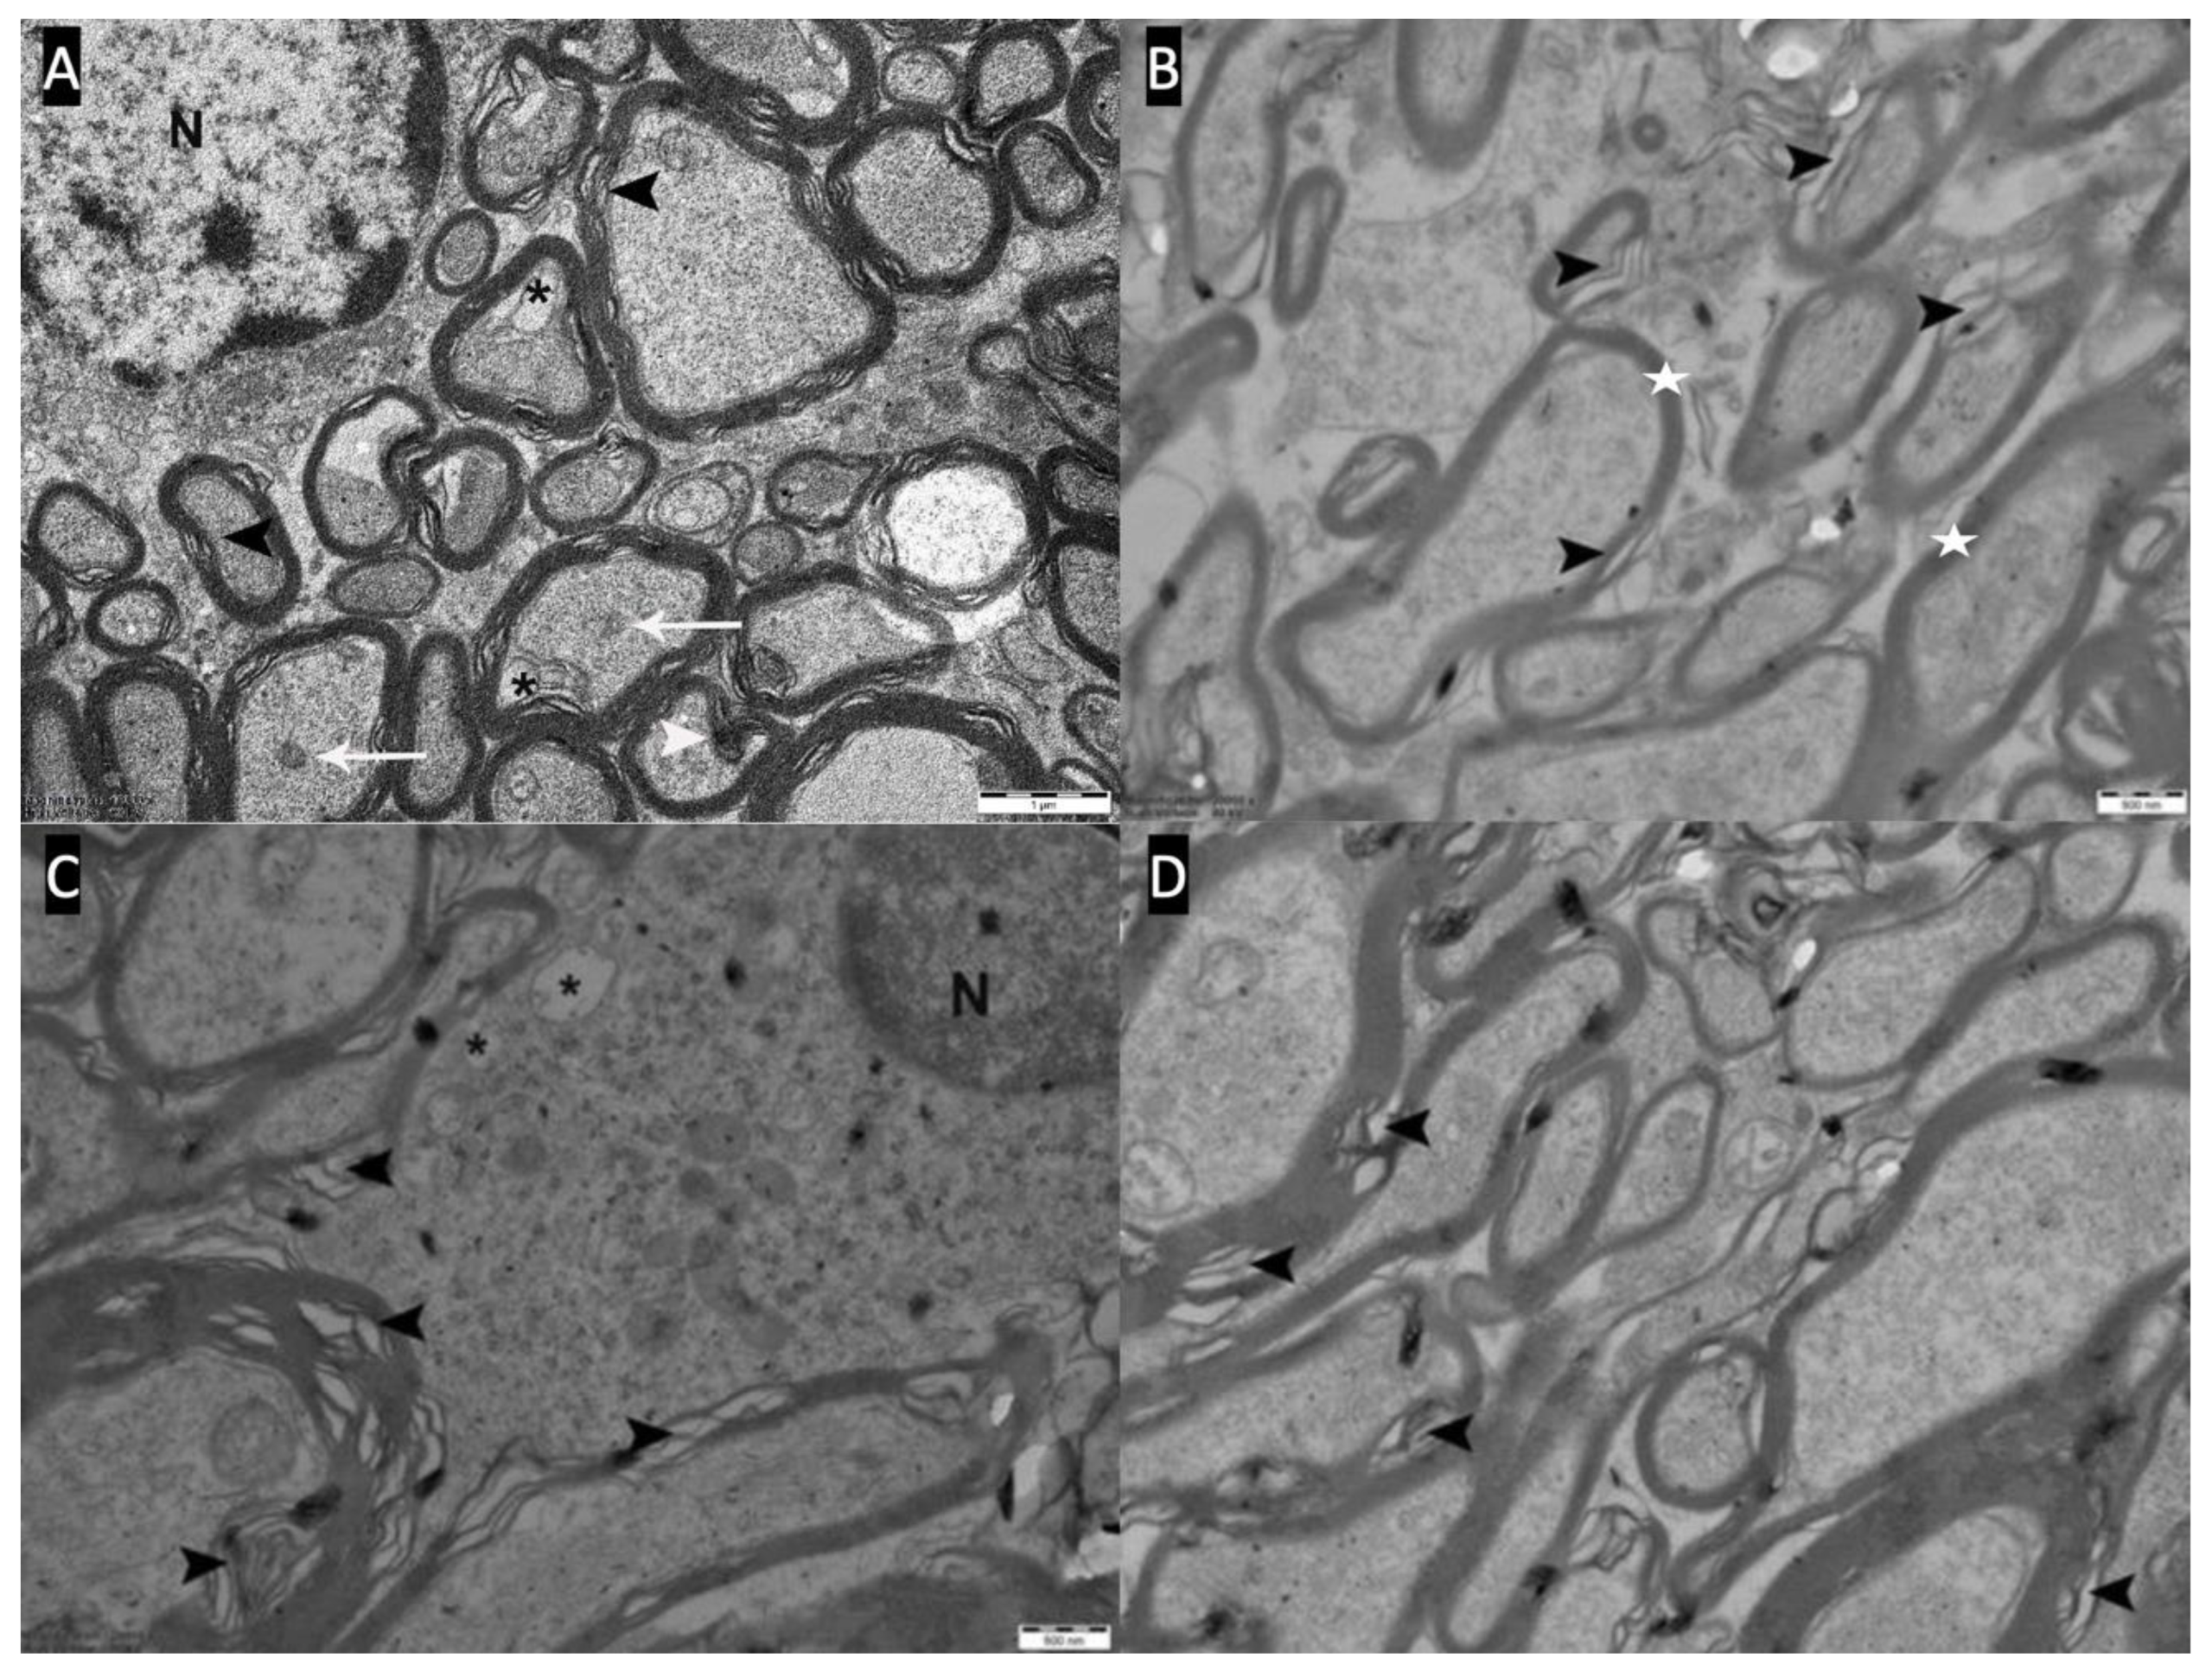

In the myricetin group (Group 4), 7 out of 8 rats (87.5%) showed slight pathological changes with a decrease in the number of vacuoles in the cytoplasm of axons and oligodendrocytes. Compared with the other groups, these 7 rats showed a decrease in dark degeneration and demyelination and axon degeneration (Figure 6).

Figure 6. A,B,C,D: Slight pathological changes (Type-I) are observed in the optic chiasm electron microscopy of the myricetin group (Group-4). There is a decrease in myelin budding and degeneration (white arrowhead), a decrease in inclusions (white arrow) and vacuoles (black asterisk) in axons and oligodendrocyte cytoplasm. Myelin sheaths surrounding the axons (white star) and occasional myelin sheath loss (black arrowhead) are seen.